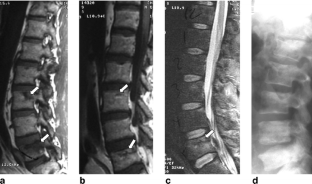

Fibrogenesis imperfecta ossium: MR imaging of the axial and appendicular skeleton and correlation with a unique radiographic appearance

We describe a distinctly unusual MR appearance of the cancellous bone never before described in a patient with biopsy-proven fibrogenesis imperfecta ossium.

Fig. 1